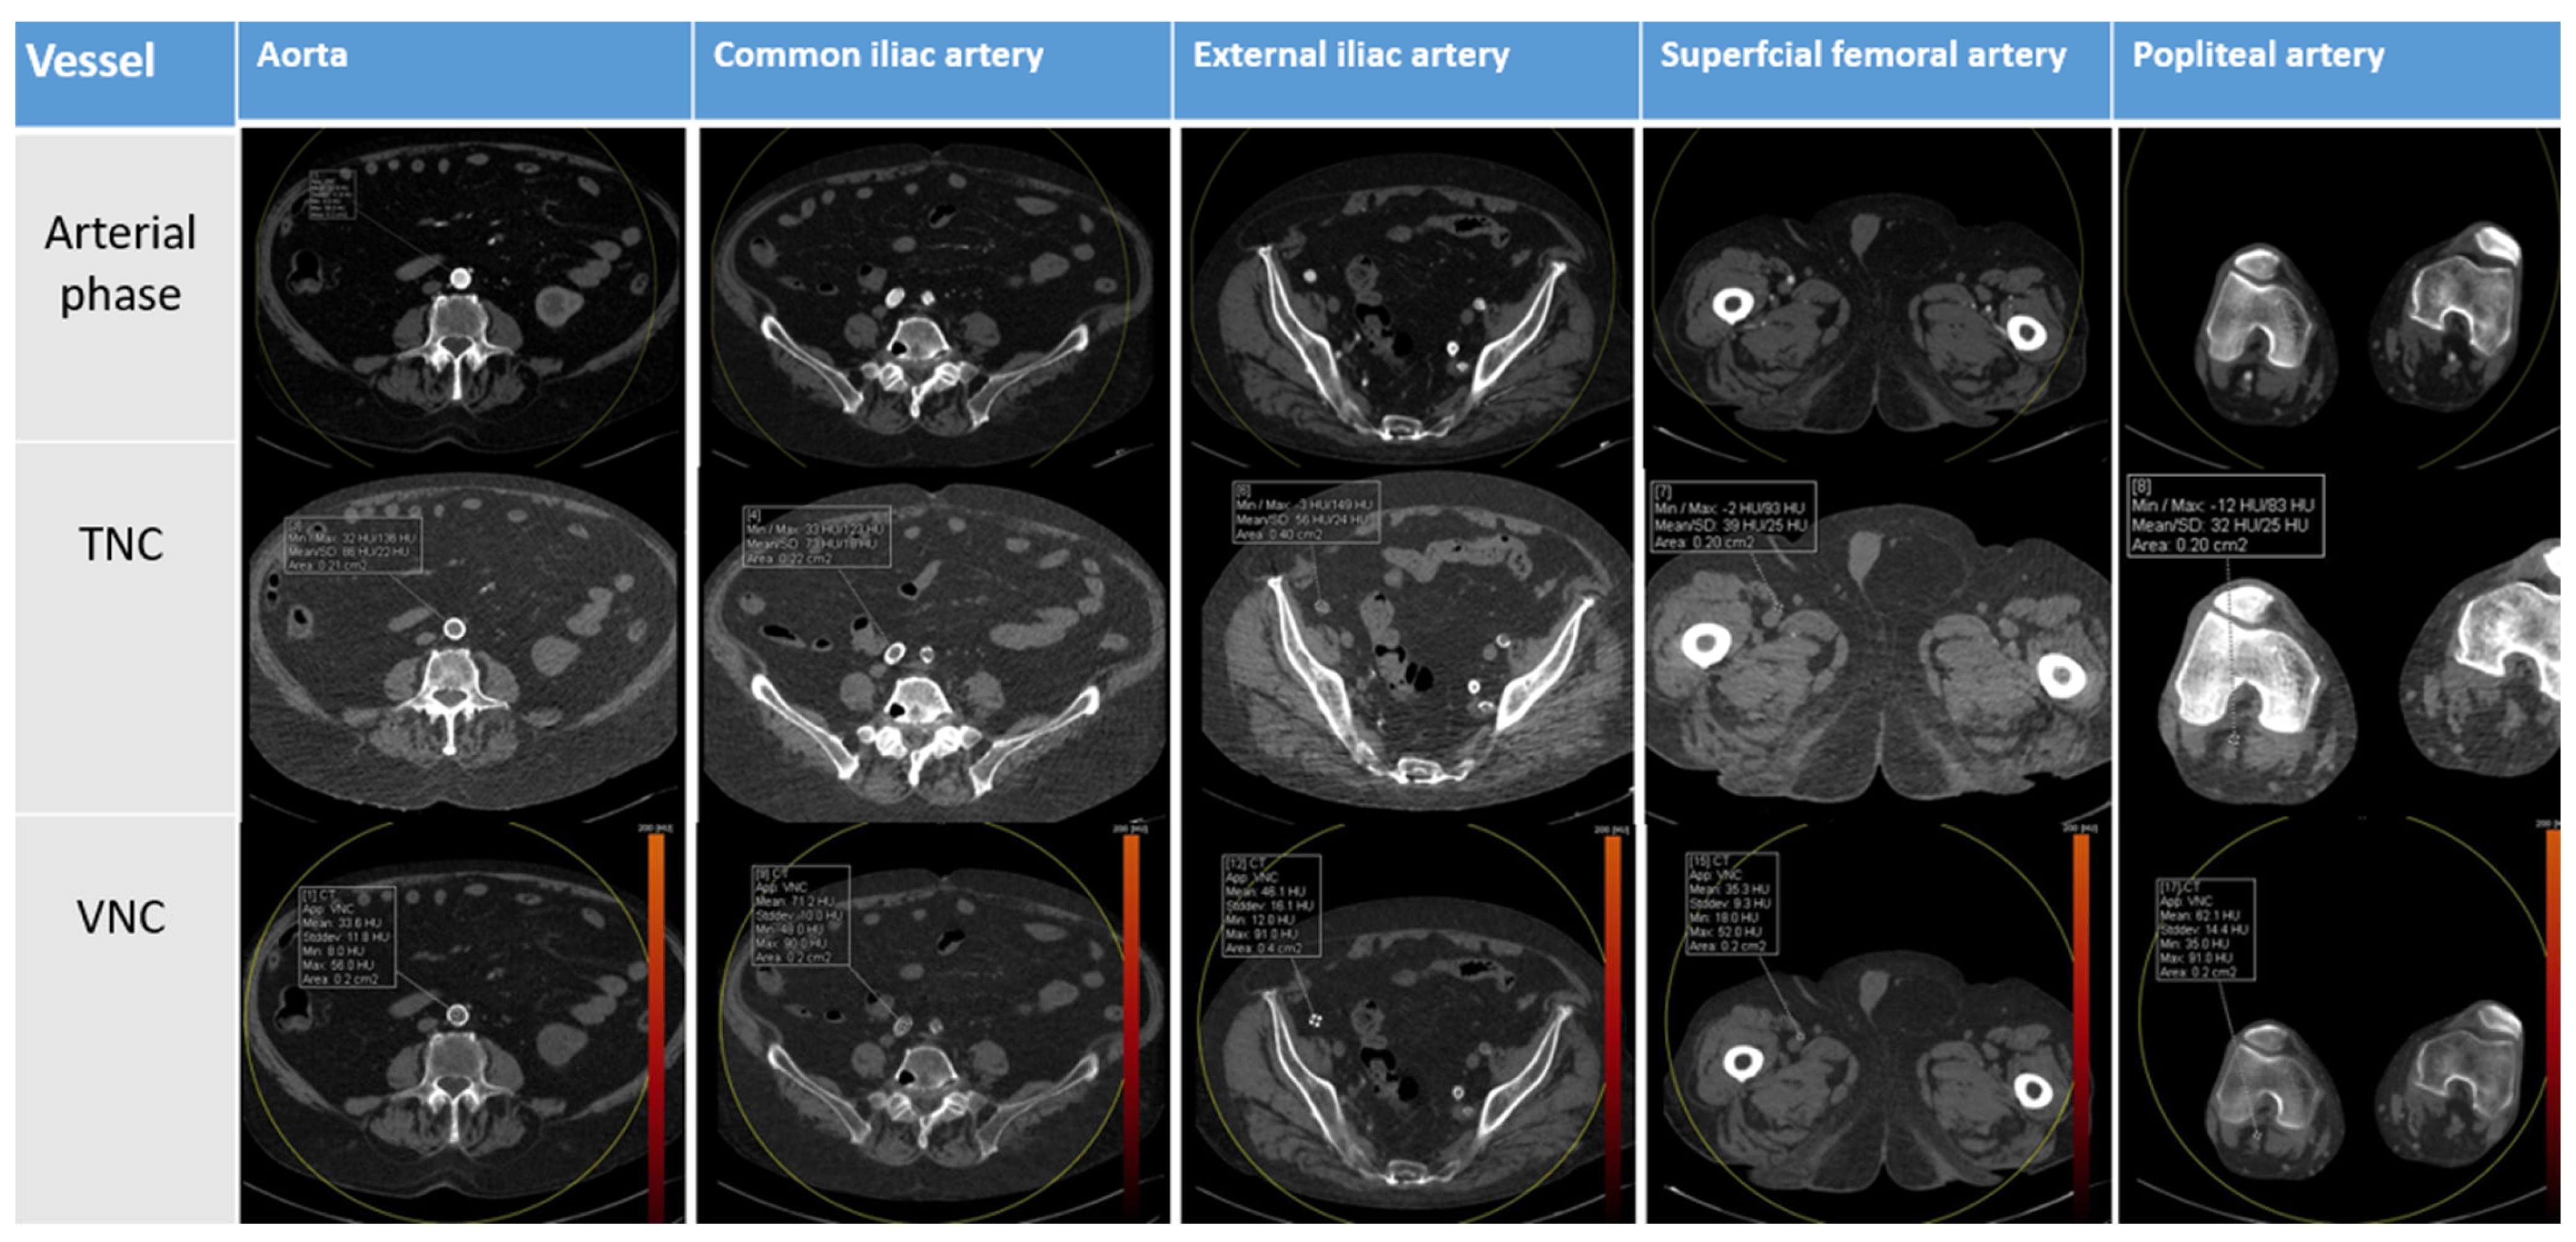

| Anatomical Region | Contrast Phase | Mean Attenuation (HU) | Standard Deviation (DS) | p |

|---|---|---|---|---|

| Aorta | TNC | 47.1 | 6.6 | <0.000 |

| VNC | 33.0 | 8.2 | ||

| AIC | TNC | 47.8 | 8.9 | <0.000 |

| VNC | 34.1 | 11.4 | ||

| AIE | TNC | 46.6 | 9.4 | <0.27 |

| VNC | 33.1 | 6.4 | ||

| AFS | TNC | 48.5 | 9.0 | <0.001 |

| VNC | 38.2 | 10.4 | ||

| AP | TNC | 49.4 | 7.8 | <0.000 |

| VNC | 40.7 | 9.6 |